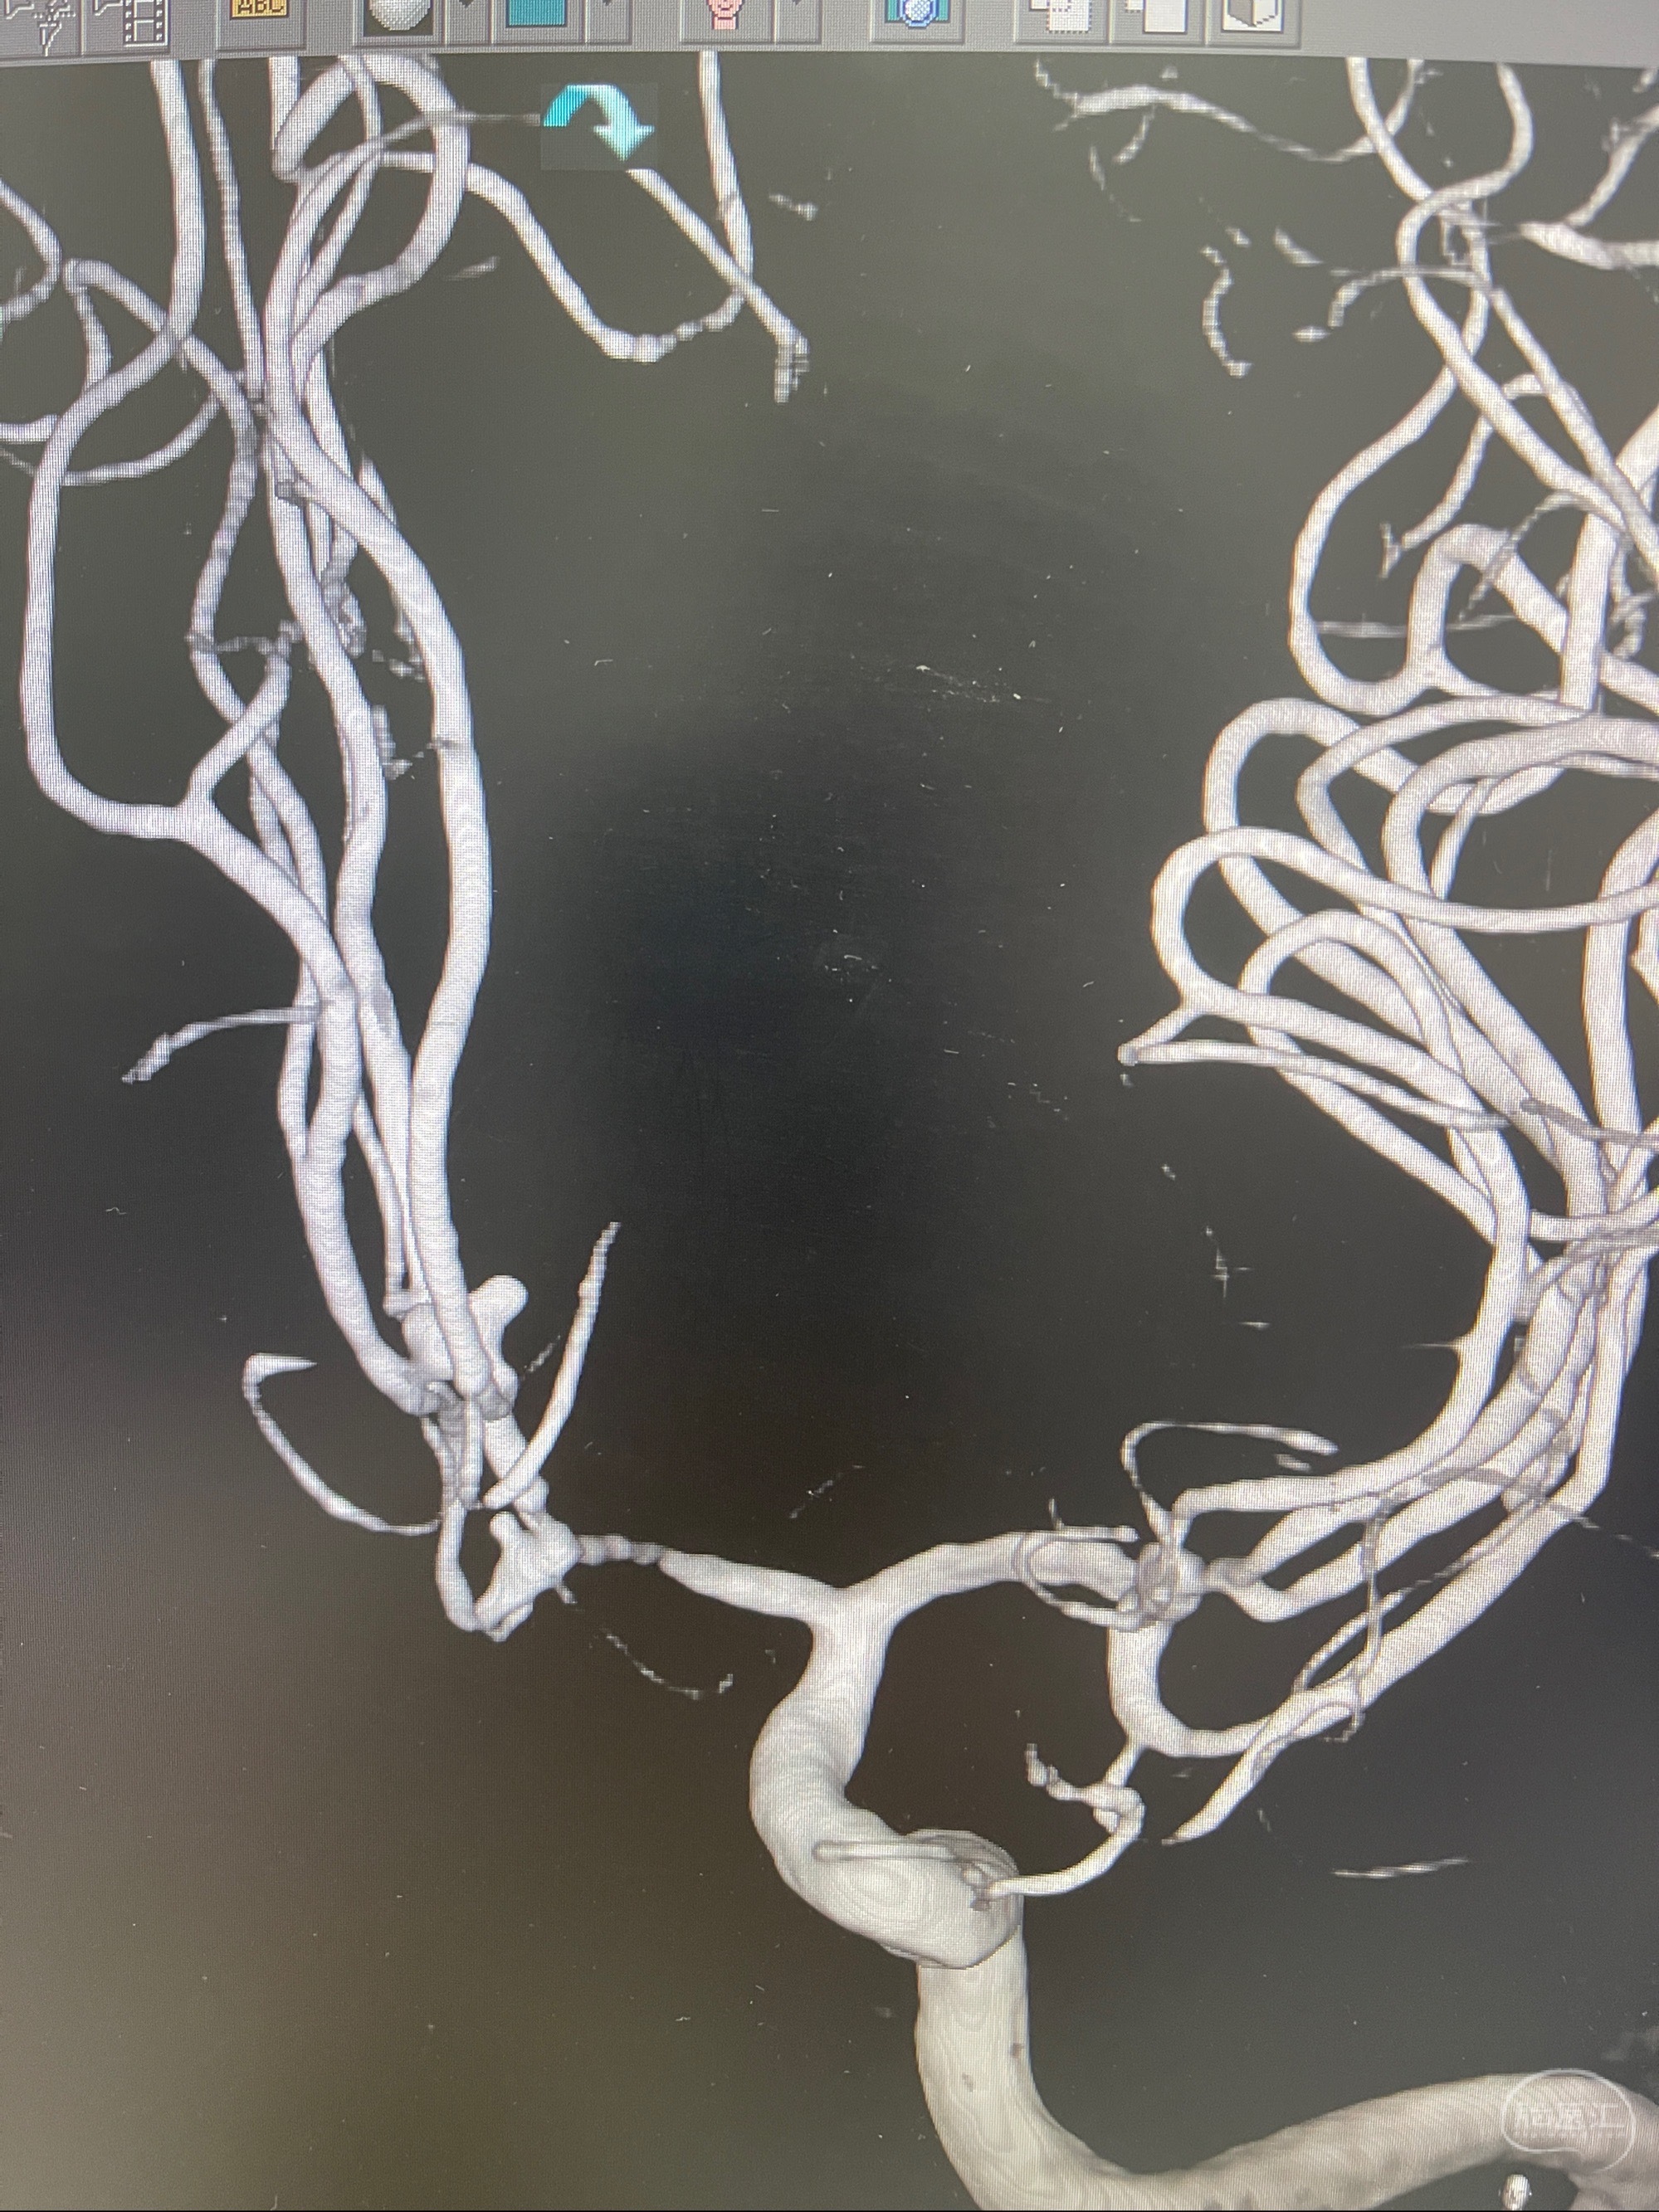

2.双侧颈内动脉狭窄

2023-08-23DSA:左侧前交通动脉瘤,左侧A3/4交界处多发动脉瘤